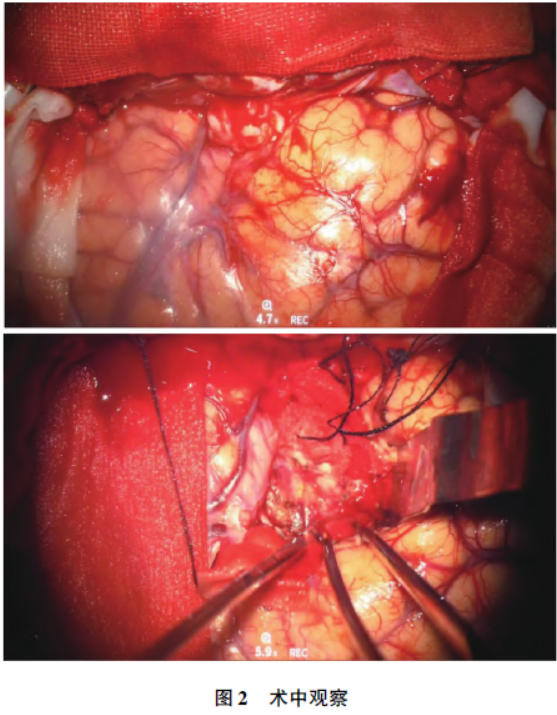

完善相关术前准备后,采用改良翼点入路行颅内占位切除术。手术过程中可见肿瘤组织由两部分组成。其中一部分呈现白色结节状,质地较韧,直径约1.5 cm,呈苍白坚硬,轮廓分明;另一部分呈暗红色,类似烂鱼肉状,二者之间由一个相对清晰的边界分隔(图2)。

白色结节状病变为小脑膜瘤,其基底附着于硬脑膜。在切断肿瘤基底后,剥离肿瘤与脑组织表面,完全切除大小约1 cm ×1 cm ×1.5 cm 的脑膜瘤。在脑膜瘤下方发现暗红色的烂鱼肉样肿瘤,主要位于左侧额叶皮层下。切开左侧额叶皮层组织,观察到肿瘤质地柔软、血供丰富,无明显包膜,表现出向周围脑组织浸润性生长的特征,镜下整块切除肿瘤。